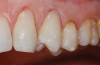

Figure  5  Loss of tooth surface and yellowing of teeth in a young patient with untreated GERD.

Figure 5

Characteristics of damage to tooth structures caused by acidity include wear on the occlusal surfaces of molars and a saucer shape on the cusps of molars (perimolysis).12 The erosion can vary from minor and subtle changes on the tooth surface, ie, loss of luster, a dull or matted look, to cupping on occlusal surfaces or incisal edges, which may extend to dentin. Usually, the erosive lesions demonstrate greater width than depth. When combined with abrasive forces or stresses, the tooth surface loss may occur at a faster rate (Figure 2, Figure 3, Figure 4 and Figure 5).

The effects of tooth surface loss vary depending on the severity of the tooth tissue loss. These effects include loss of thickness of enamel and exposure of the underlying dentin, translucency, and yellowing. Also, the occlusal surfaces may display wear facets, or the cusps may flatten.